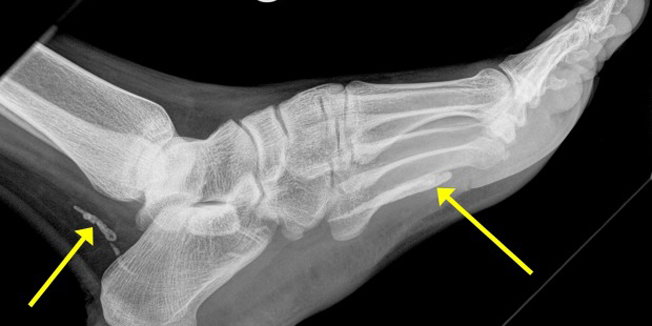

Naime, poslije obavljenog rendgena dr. Jonathan Darby iz bolnice Sv. Vincent u Melbournu obavijestio je svog pacijenta da mu se u nozi nalazi opasan nametnik koji može narasti do jednog metra te da zasigurno živi u njemu godinama.

Nametnik Dracunculus medinensis, poznat kao gvinejski crv, mali zmaj ili vatrena zmija, pronađen u nozi pacijenta dr. Darbyja jako je rijedak, a nastanjuje samo neke dijelove Afrike.